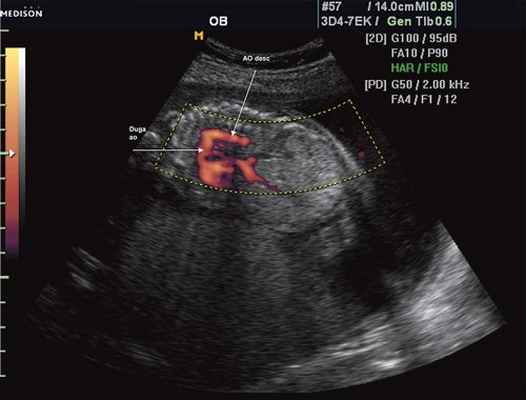

Стеноз перешейка аорты, проявляющийся в систолу при цветовом допплеровском исследовании в сочетании с двумерной ЭхоКГ (сканирование из супрастернальной позиции вдоль оси дуги аорты).

Отчетливо виден непосредственный переход ламинарного кровотока в дистальном отделе дуги аорты (dAJA) в турбулентный ток крови (зеленый цвет) в области стеноза (стрелка), локализующегося ниже места отхождения левой подключичной артерии (звездочка).

AOA - восходящая аорта, Tbc - плечеголовной ствол, IAcc -левая общая сонная артерия, dAOA - дистальный отдел дуги аорты, DAO - нисходящая аорта. Спектральная кривая кровотока при стенозе перешейка аорты, полученная при ло-цировании аорты из супрастернальной позиции.

Максимальная скорость кровотока достигает 4 м/с, а соответствующий ей градиент давления равен 64 мм рт.ст.

Типичным для стеноза перешейка аорты является реверсивный кровоток, который сохраняется до начала следующей систолы.

Мгновенный градиент давления, рассчитанный таким образом, отчетливо выше, чем измеренный с помощью инвазивных методов исследования.